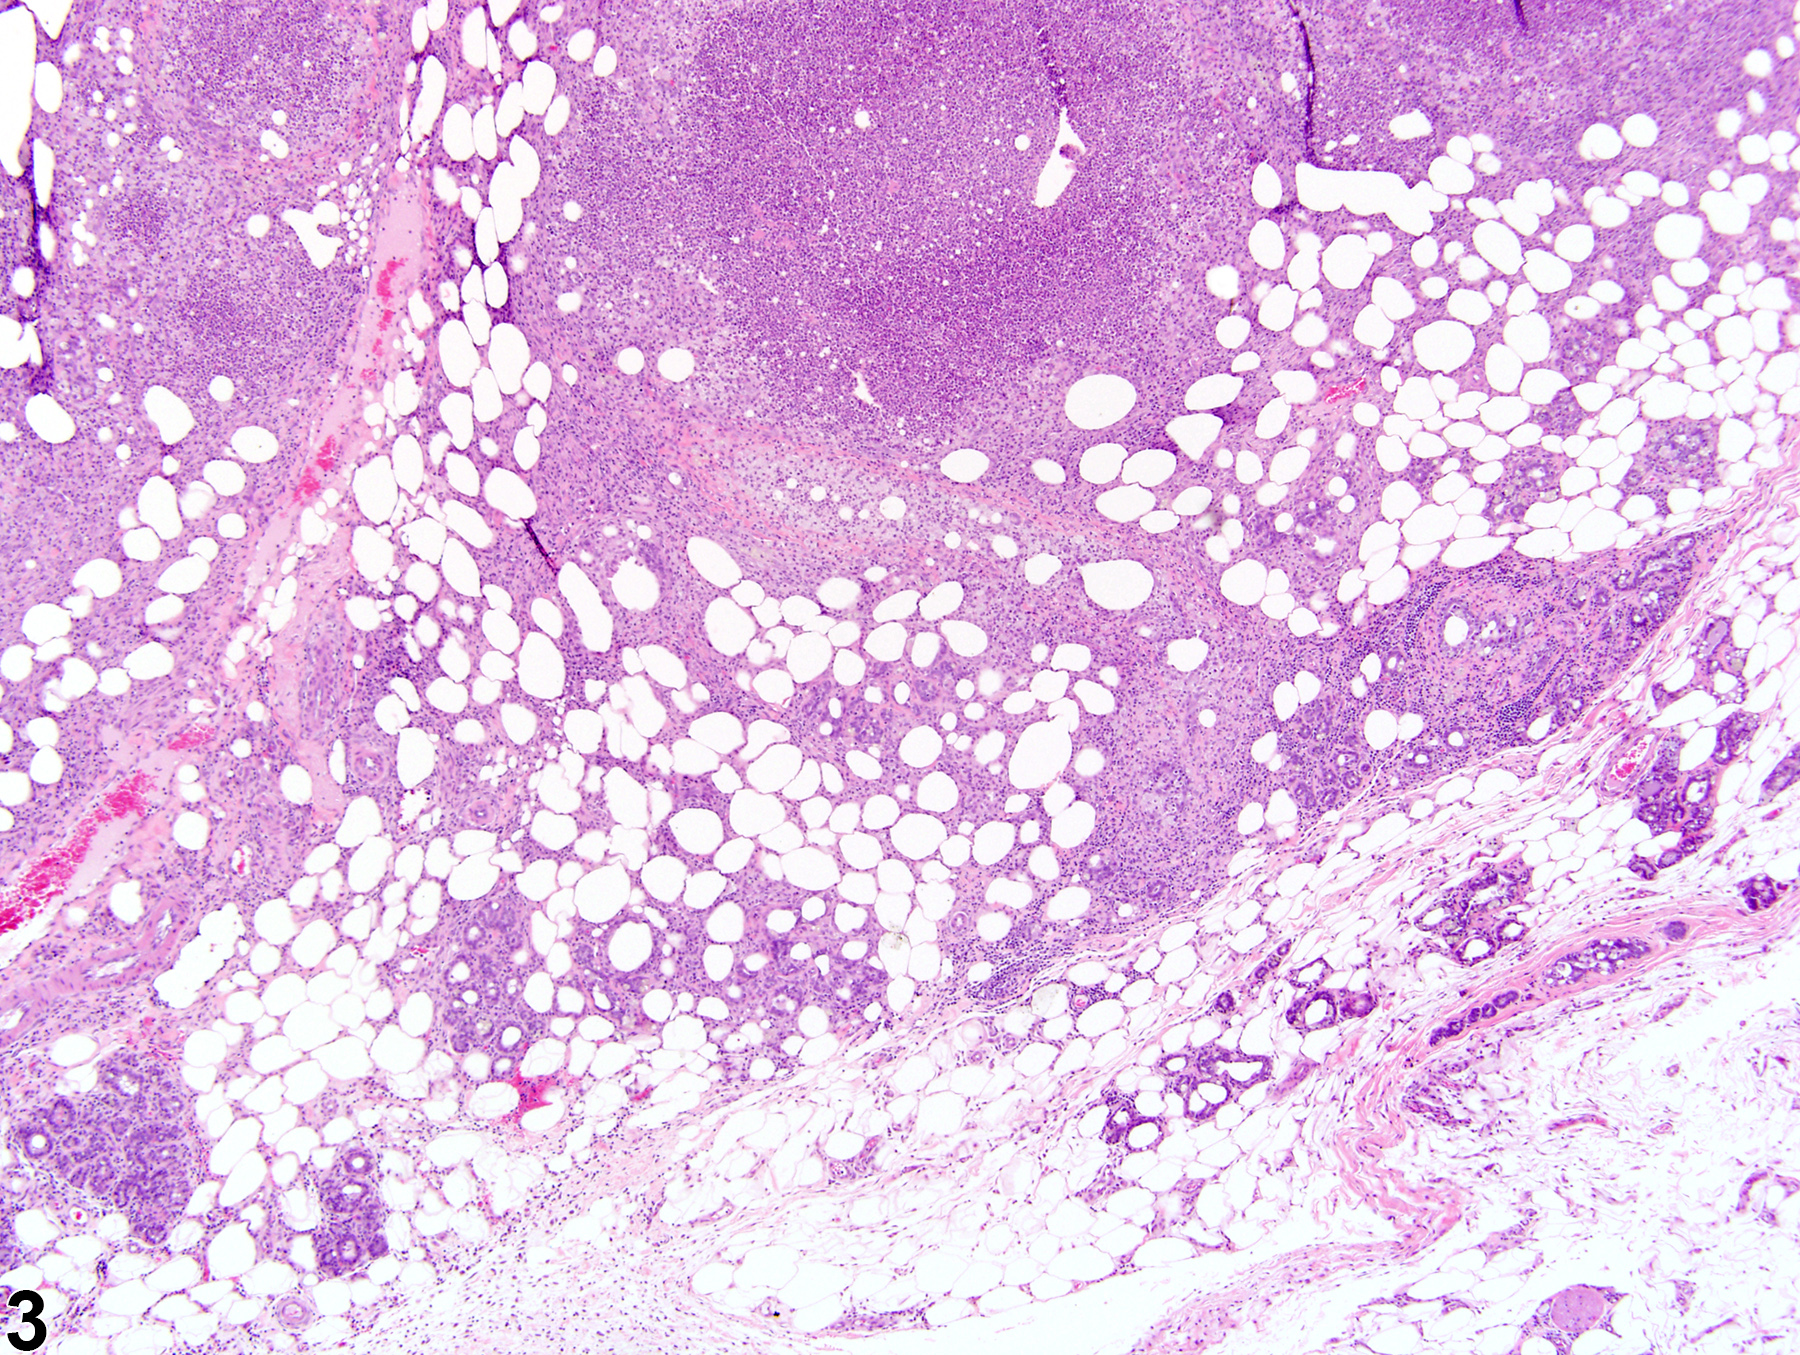

Acute inflammation (Figure 1 and Figure 2) in the mammary gland is characterized by infiltration of neutrophils, which may be accompanied by eosinophils and, to a lesser extent, macrophages, mast cells, lymphocytes, and plasma cells. These cellular infiltrates are generally accompanied by vascular congestion; edema; the accumulation of serous, mucous, or fibrinous exudates; and sloughed epithelial cells in tubular and/or alveolar lumina. Suppurative inflammation (Figure 3 and Figure 4) of the mammary gland is characterized by discrete pockets of degenerate neutrophils and cellular debris. Evidence of chronicity, such as fibrosis and lymphoplasmacytic infiltrates, may also surround these pockets. Chronic inflammation of the mammary gland is characterized by the presence of mononuclear cells (lymphocytes, plasma cells, and macrophages) and may be accompanied by epithelial cell regeneration, hyperplasia and/or metaplasia, and fibrosis. Chronic active inflammation of the mammary gland is characterized by the coexistence of elements of chronic inflammation (lymphocytes, macrophages, regeneration, hyperplasia, and fibrosis) and superimposed acute inflammation (neutrophilic and/or eosinophilic). Granulomatous inflammation is characterized by an accumulation of plump macrophages (epithelioid cells) organized in interlacing bundles, with variable numbers of multinucleated giant cells, lymphocytes, plasma cells, or neutrophils and may be accompanied by fibrosis epithelial cell regeneration, hyperplasia, and/or metaplasia. Granulomatous inflammation is commonly seen in rats associated with rupture of dilated ducts. Other etiologic agents may be present and induce inflammatory changes (e.g., fungi, foreign bodies, etc.). All forms of inflammation may be accompanied by associated lesions, including edema (though this is more commonly associated with acute inflammation), epithelial hyperplasia, neovascularization, or hemorrhage with or without hemosiderin-containing macrophages.

Mammary gland - Inflammation, chronic active in a female B6C3F1/N mouse from a chronic study. Mammary gland inflammation (featuring infiltrates consisting mainly of neutrophils) is located primarily in the stroma between alveoli.